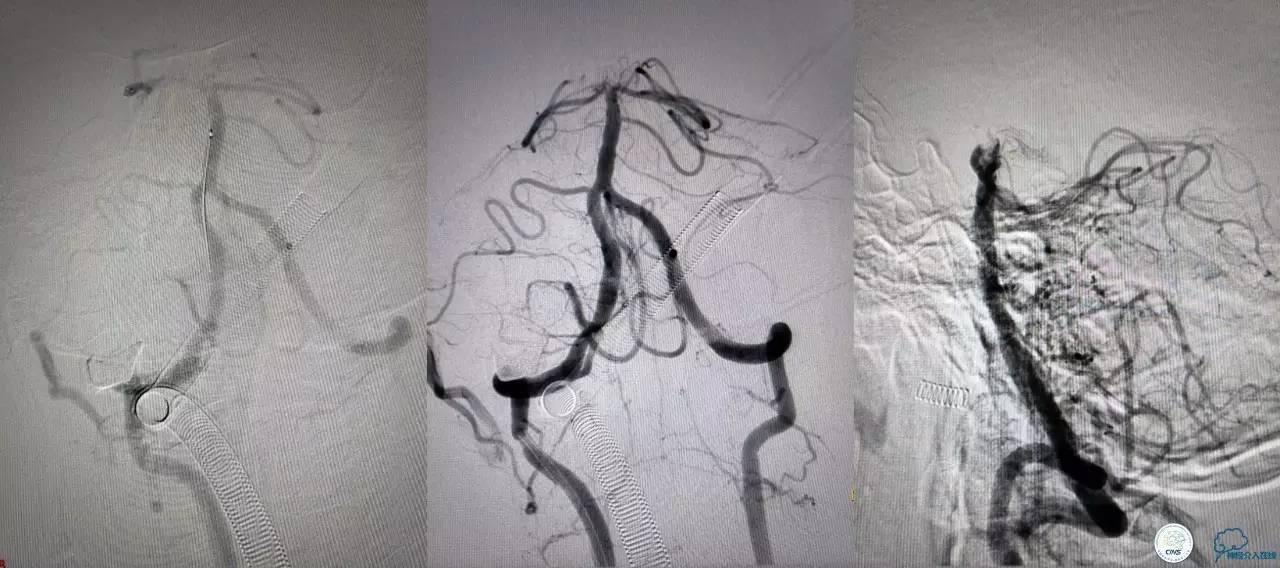

血栓负荷还是很大,左侧大脑后再通,但右侧大脑后又闭塞,只能第五次取栓,支架放到右侧大脑后动脉更远。

好大的血栓,支架释放后,血管无复流,拉一把!

没错,没看错!血管成功实现再通,术中取栓的栓子如下。

术后生命体征平稳,成功撤呼吸机,肌力较前好转,复查头颅CT:

右侧丘脑高密度影,右侧枕叶可能也有梗死,祈祷慢慢恢复吧!